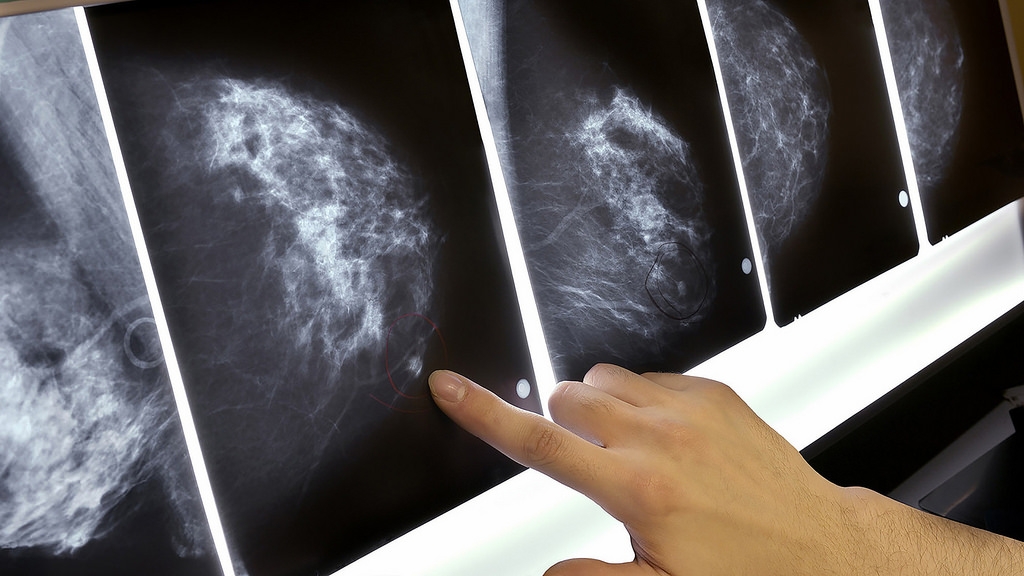

El especialista resaltó que cualquier tumor que se detecta en etapas tempranas, se erradica en 80 por ciento de los casos. La realidad es que todavía 70 por ciento se detecta en etapas avanzadas.

En este caso, igual que en mama y próstata en los hombres, las pruebas clínicas identifi-can las células cancerígenas desde las etapas iniciales, con lo que los pacientes están en posibilidades de controlar e incluso curarse de manera definitiva.